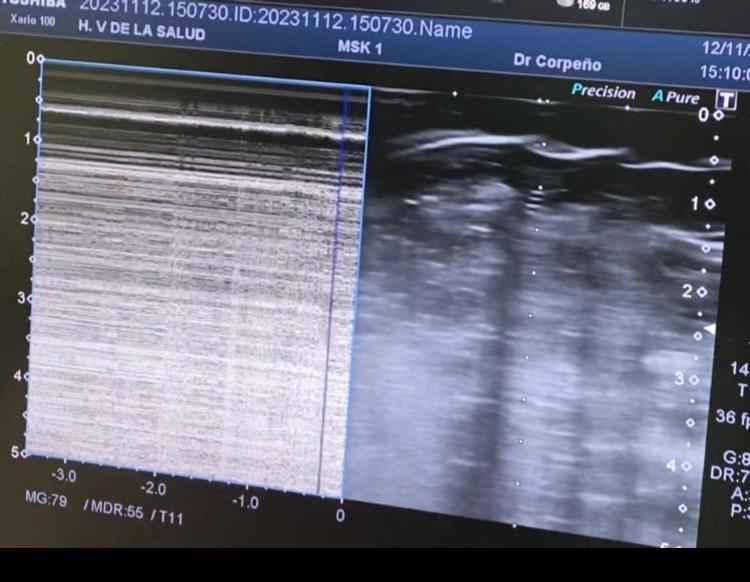

Se trata de una mujer de 46 años que acude por presentar contusión costal izquierda tras caída fortuita de madrugada acude a urgencias 10 horas después de la caída refiriendo dolor costal, no disnea. Exploración Física TAS: 140,0 TAD: 95,0 FC: 95 FR: 22 Saturación de Oxígeno: 97 no IY. TORAX: Dolor a punta de dedo anterolateral izquierdo, no crepitación, no enfisema subcutáneo, MVC disminuido en posterior y lateral. Se realiza ecografía clínica a pie de cama observando líneas A, no líneas B, no deslizamiento pleural con signo de código de barras, ausencia de pulso pulmón. Se realiza Rx de parilla costal y tórax: Fractura de 6 arco costal izquierdo y neumotórax izquierdo.

Se trata de una mujer de 46 años con dolor costal, sin disnea, ni repercusión ventilatoria al momento de su llegada pero que mediante ecografía a pie de cama se reveló un neumotórax oculto (signo de código de barras). La paciente requirió drenaje torácico ecoasistido logrando expansión pulmonar.

En este caso, la ecografía clínica permitió identificar hallazgos clave: ausencia de deslizamiento pleural, presencia de líneas B, signo de código de barras y ausencia de pulso pulmón. Aunque no se observó el pulso pulmón, que tiene menor sensibilidad, se confirmó el diagnóstico mediante radiografía de tórax, evidenciando fractura costal y neumotórax traumático izquierdo. La colocación de un tubo de tórax ecoasistido permitió la expansión parcial del pulmón y facilitó un manejo seguro, con ingreso hospitalario para seguimiento y monitorización.